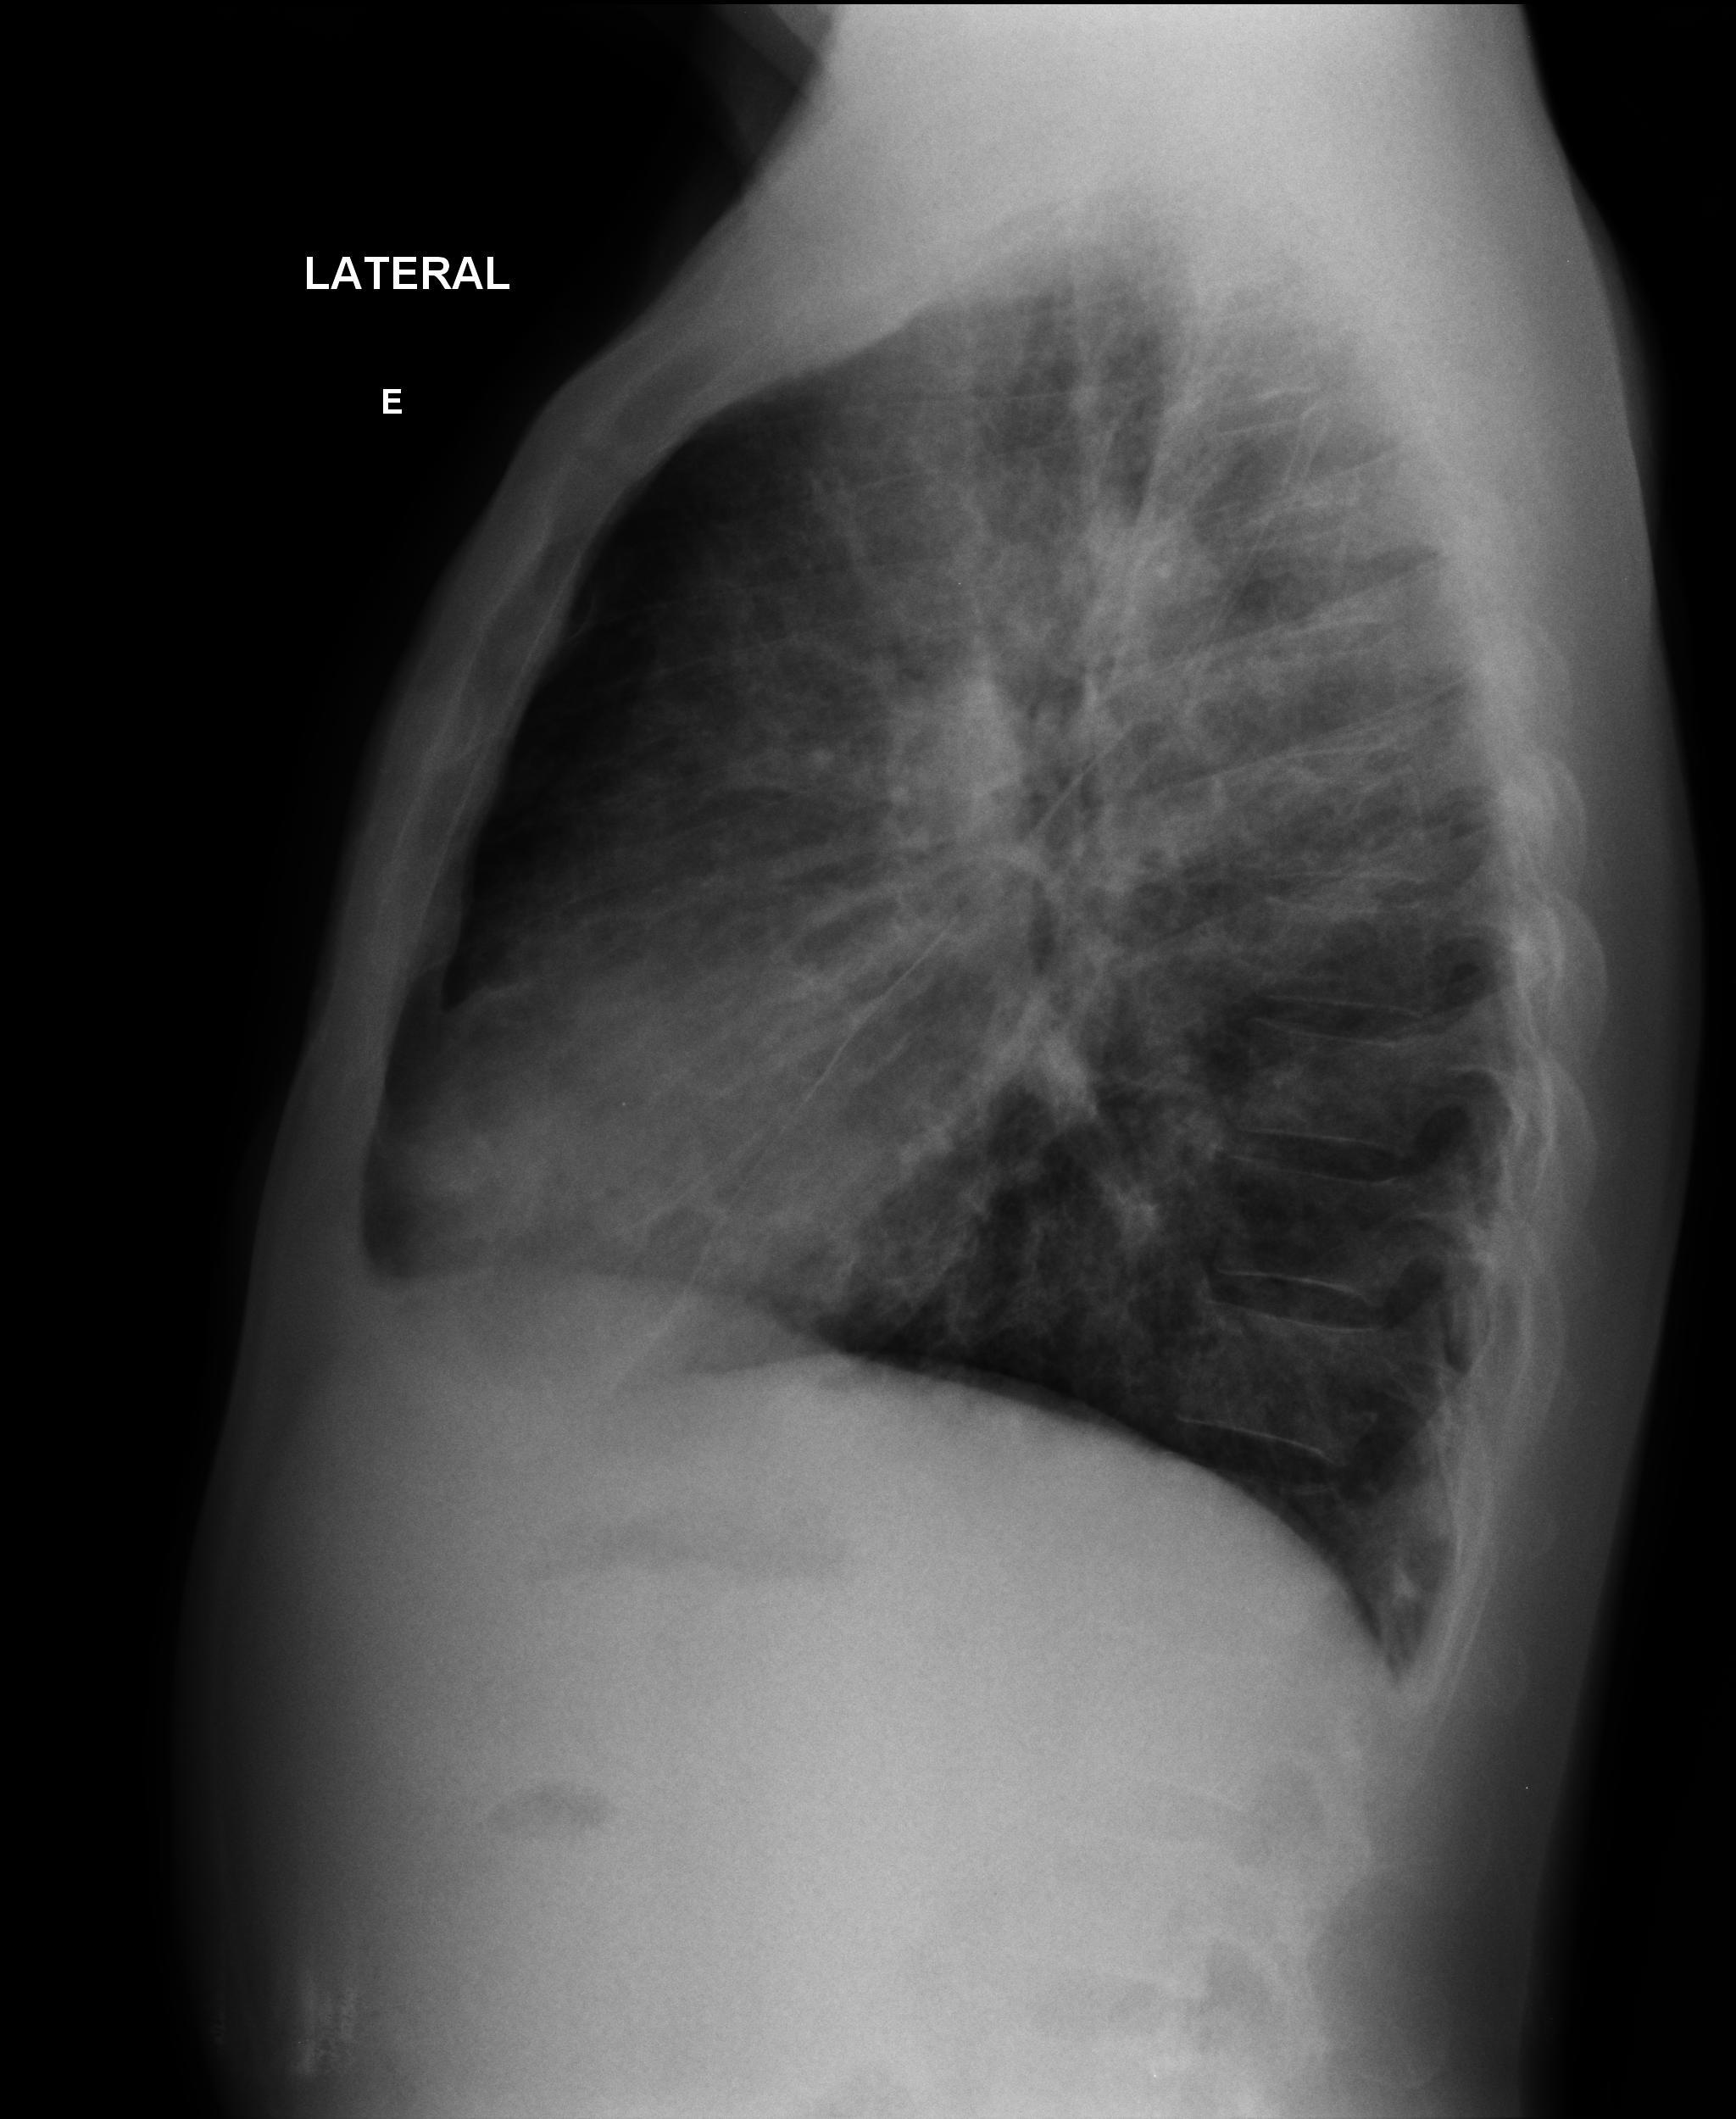

Caso Número 4/2018: “Uma sessão interativa de casos em radiologia torácica – Parte 1”

Caso relatado na Reunião de Discussão de Casos Clínicos do Hospital Universitário Prof. Polydoro Ernani de São Thiago, iniciada pelos Profs. Jorge Dias de Matos, Marisa Helena César Coral e Rosemeri Maurici da Silva, em julho de 2017. No dia 14 de junho de 2018, no auditório do HUPEST, realizou-se a apresentação e discussão do caso cujo registro é apresentado a seguir. Trata-se da discussão de onze casos em radiologia torácia, de forma interativa com a plateia, e assim ocorre também neste artigo.